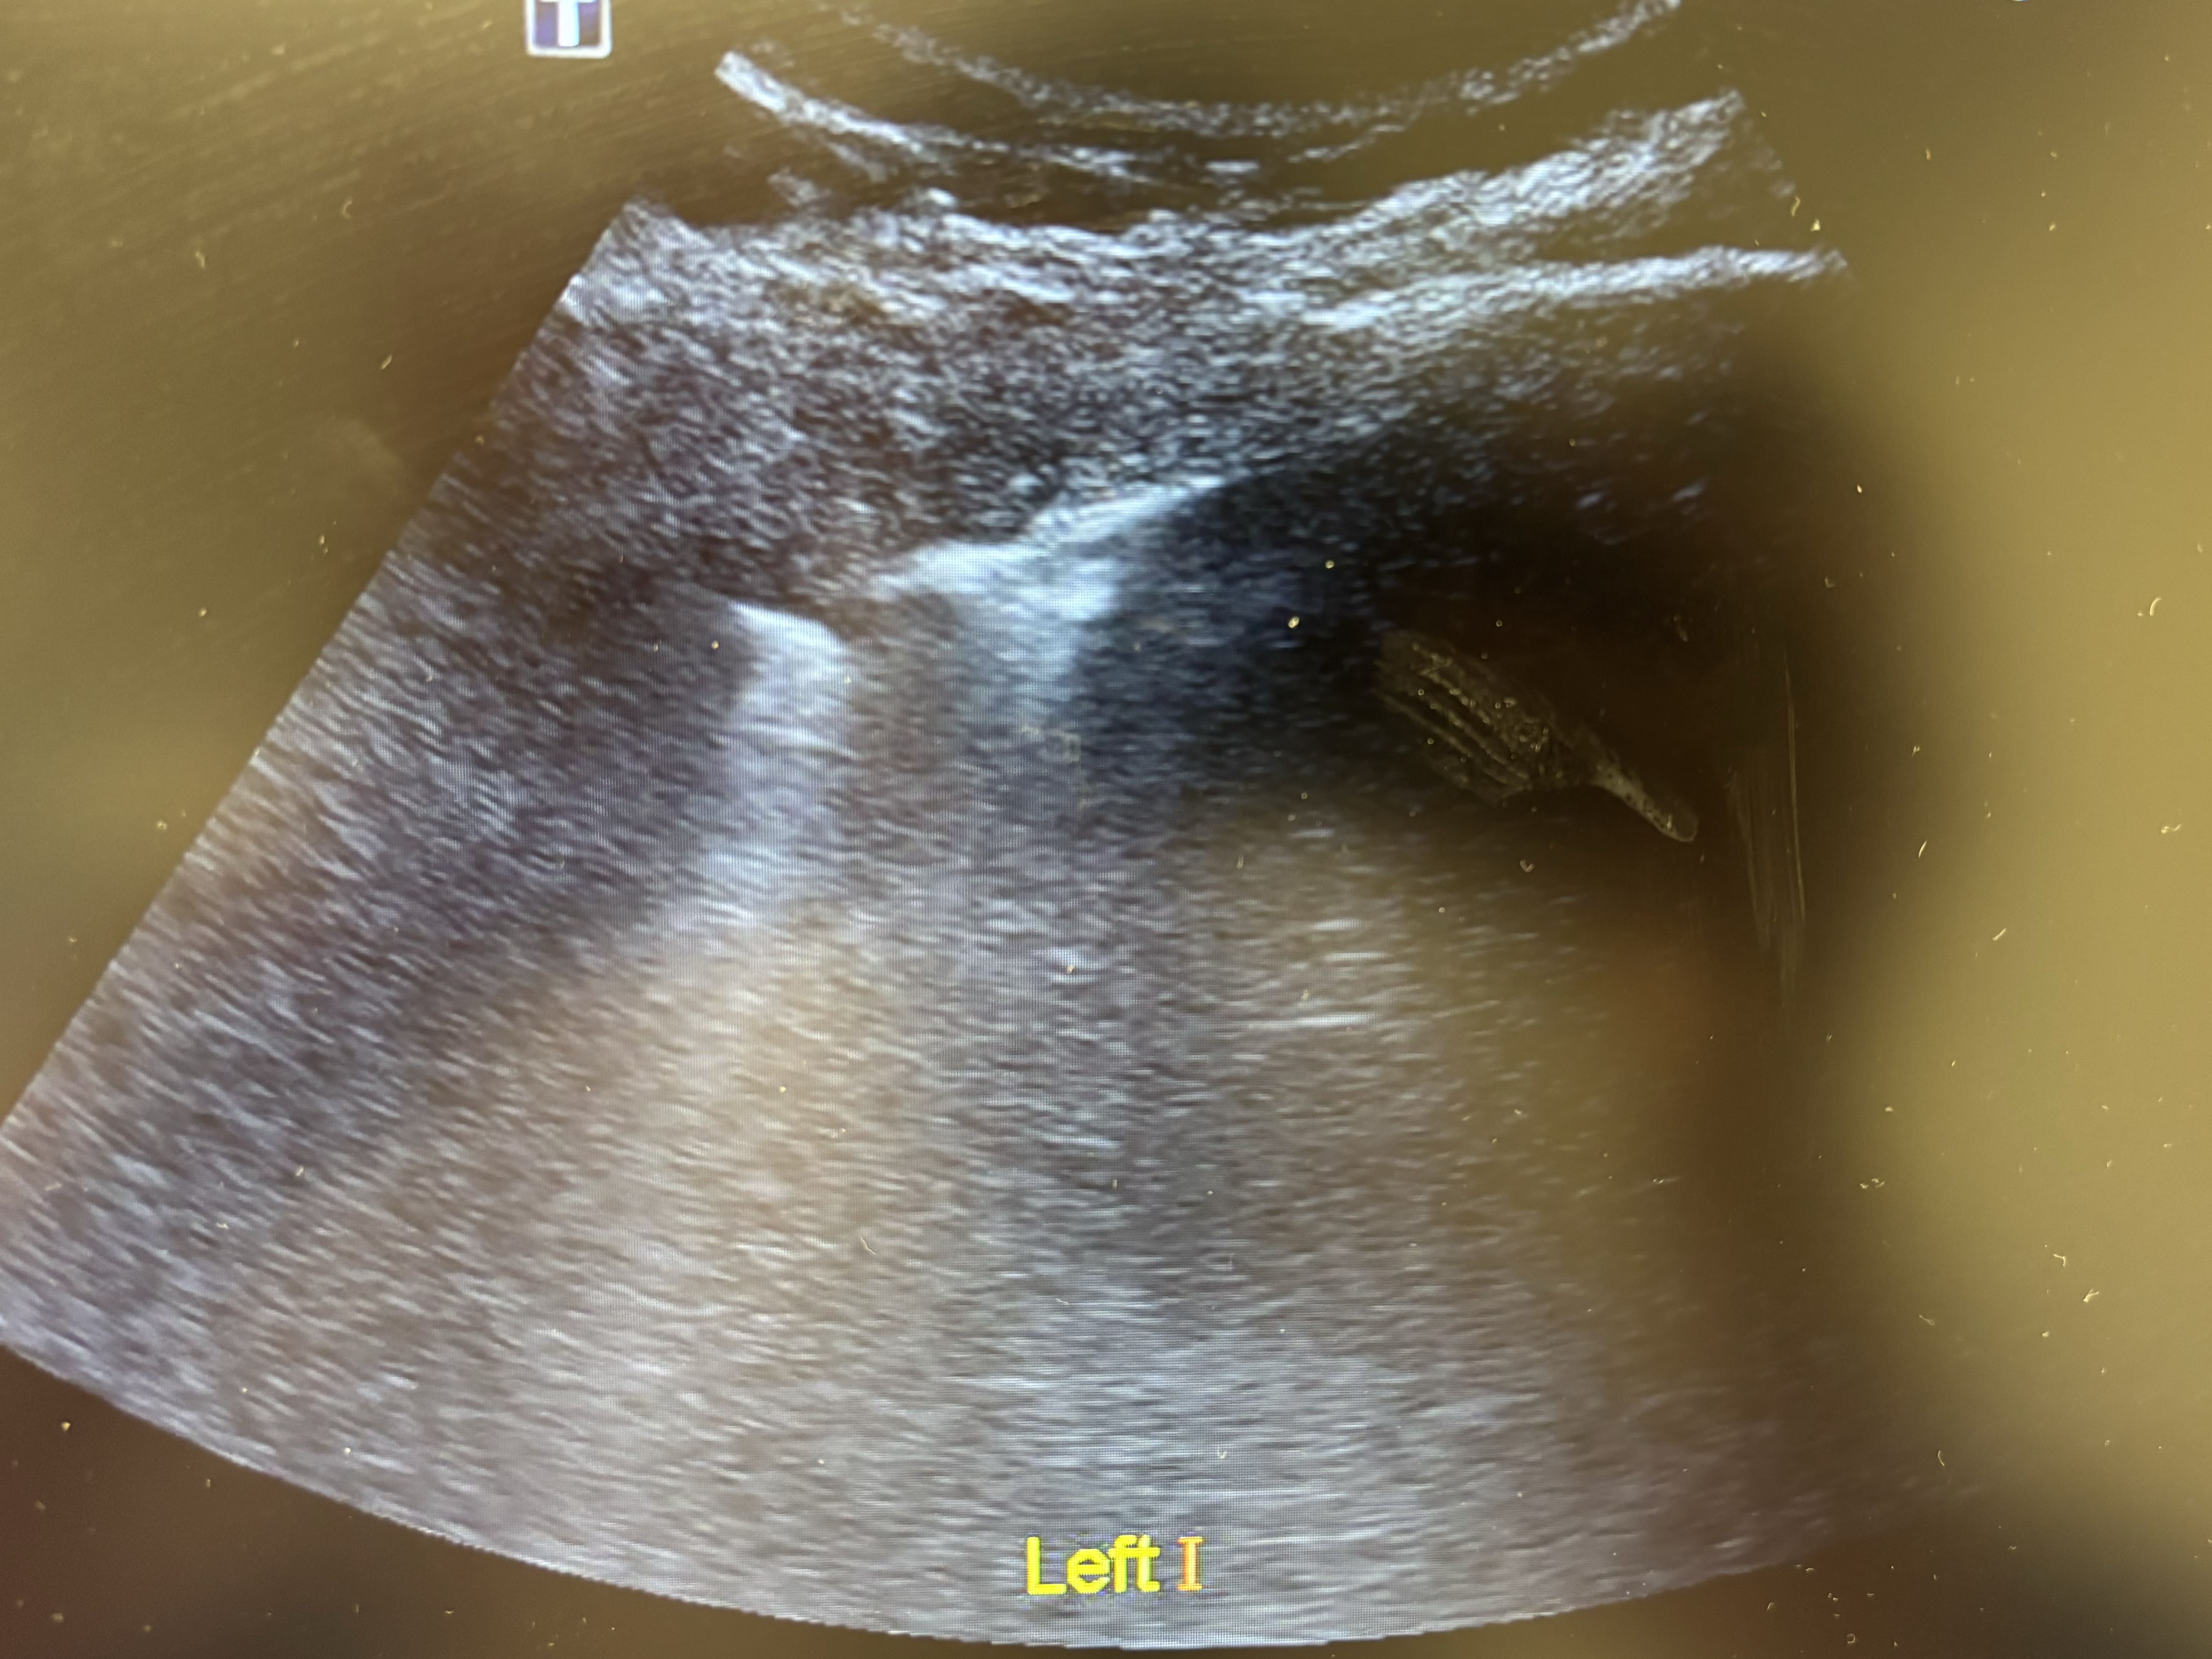

Antes de solicitar otras pruebas complementarias, se decide realizar ecografía clínica pulmonar. Se detecta un patrón intersticial focal en base izquierda, con condensación basal, mínimo derrame pleural y líneas B periféricas. Deslizamiento pleural conservado bilateral.

Como curiosidad, las neumonías suelen presentarse como área hiperecoicas o con sombras acústicas en casos más graves.